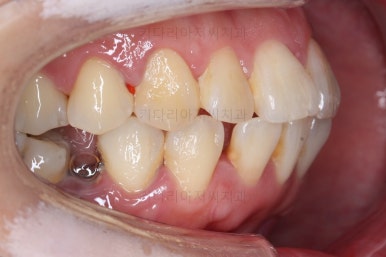

위아래 좌우 치아가 없는 위치가 모두 달랐지만 교합도 잘 구성했고요.

아무래도 좌우 치아 크기들이 다르다 보니(뽑은 치아가 다르니) 중앙선은 100% 일직선은 안맞더라도 매우 정상 범주로 마무리를 할 수 있었습니다.

특히 어금니에 보이던 충치도 깔끔하게 마무리 했고요.

이제 부산교정치과 전후 비교해 보겠습니다.

치아배열, 틈새, 교합, 중앙선, 입매, 심지어 충치까지 깔끔히 잘 마무리 되었습니다.